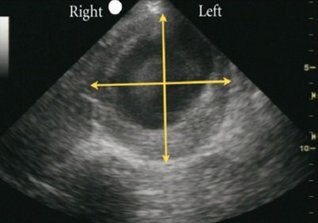

- Měření vždy zevní-zevní kontura cévy včetně trombu kolmo na dlouhou osu aneuryzmatu. Příklad na obrázku